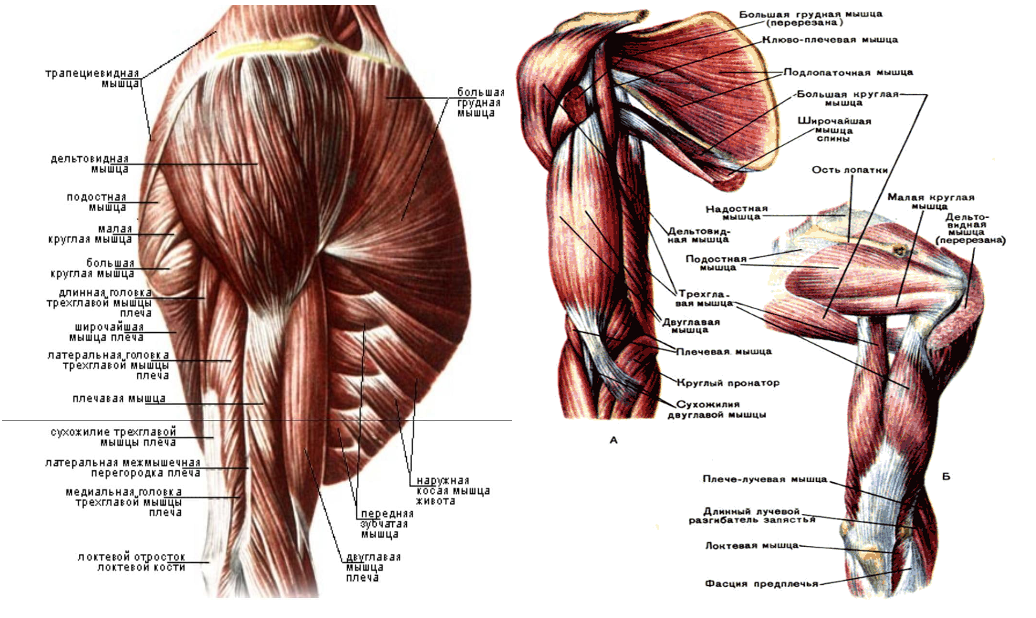

Фотографии поддельтовидной мышцы плечевого сустава

Раздел: Образы вокруг